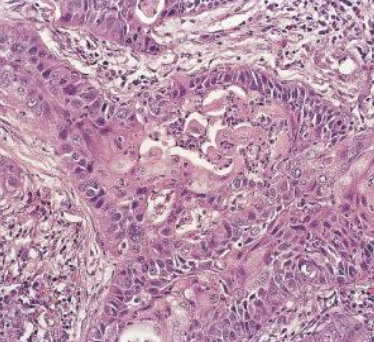

Carcinoma de células escamosas

<p>Carcinoma de células escamosas, nivel de diferenciación</p>

Carcinoma de células escamosas, nivel de diferenciación

Pobremente diferenciado

Moderadamente diferenciado

Bien diferenciado